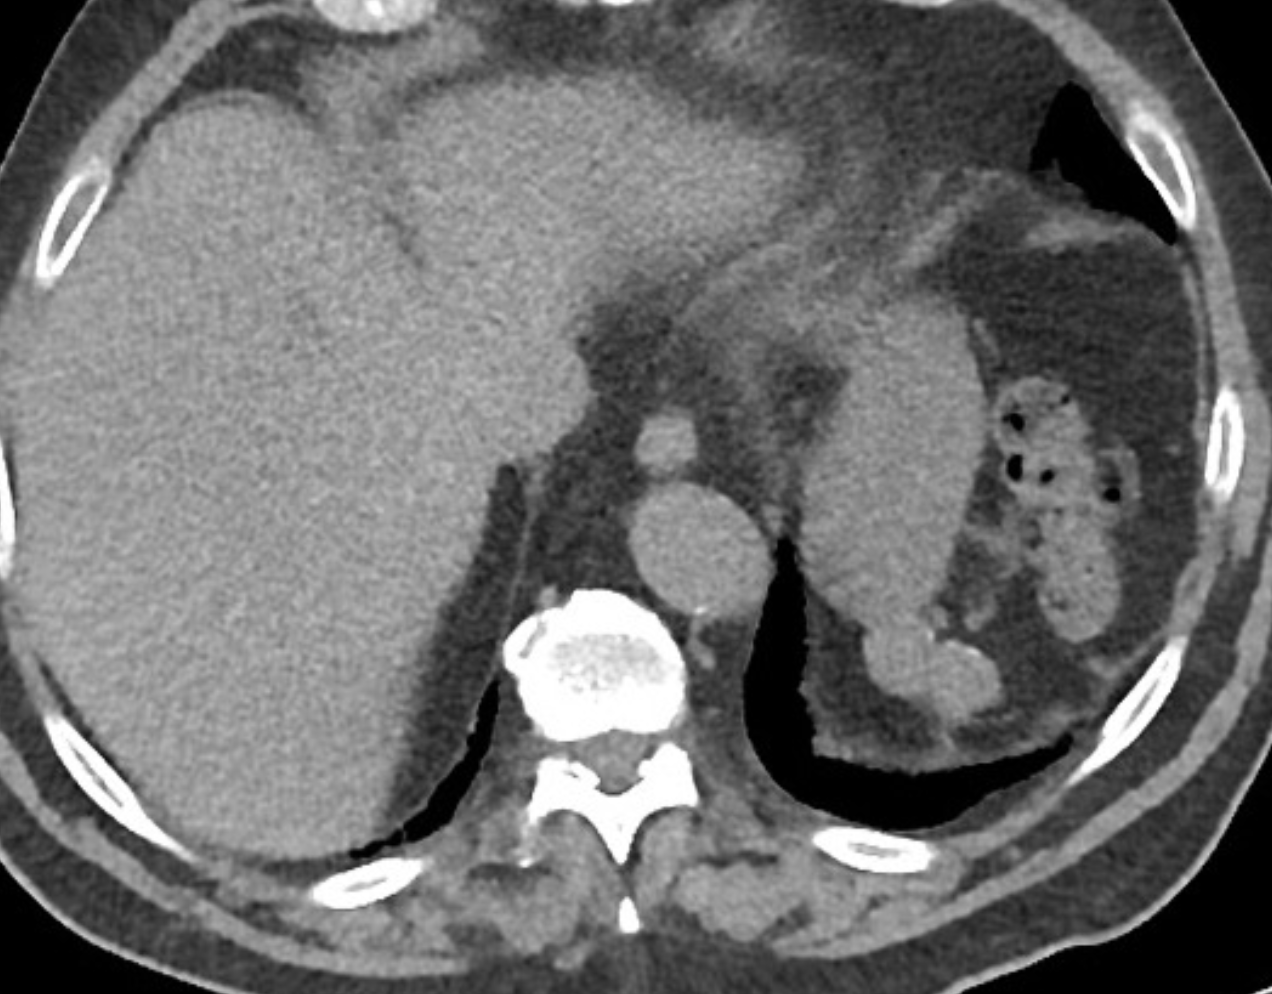

what nuc med scan can be used to diagnose this condition?

Splenosis is one type of ectopic splenic tissue (the other being accessory spleen). It is an acquired condition and is defined as autoimplantation of one or more focal deposits of splenic tissue in various compartments of the body.

Abdominal splenosis is seen after abdominal trauma or surgery (e.g. splenectomy). It results from seeding of the peritoneal cavity with splenic tissue which recruits local blood supply. The ectopic splenic foci are typically small, sessile (as they grow on serosal/peritoneal surfaces) and multiple. They may grow over time to become quite sizeable. If located only intrahepatically, they can cause serious diagnostic problems.

CT

They are typically rounded or sessile nodules, and have density and enhancing characteristics similar to the rest of the spleen, or expected density of the spleen if there has been a splenectomy.

Tc-99m-tagged heat-damaged RBC scan (Tc-99m-DRBC) with autologous erythrocytes shows accumulation in the abdominal cavity, consistent with intra-abdominal splenosis.

Case Discussion

Main concern for intra-abdominal lesions found on CT scan was for metastatic disease. Using heat treated RBC confirmed the functioning splenosis at the various abdominal sites.